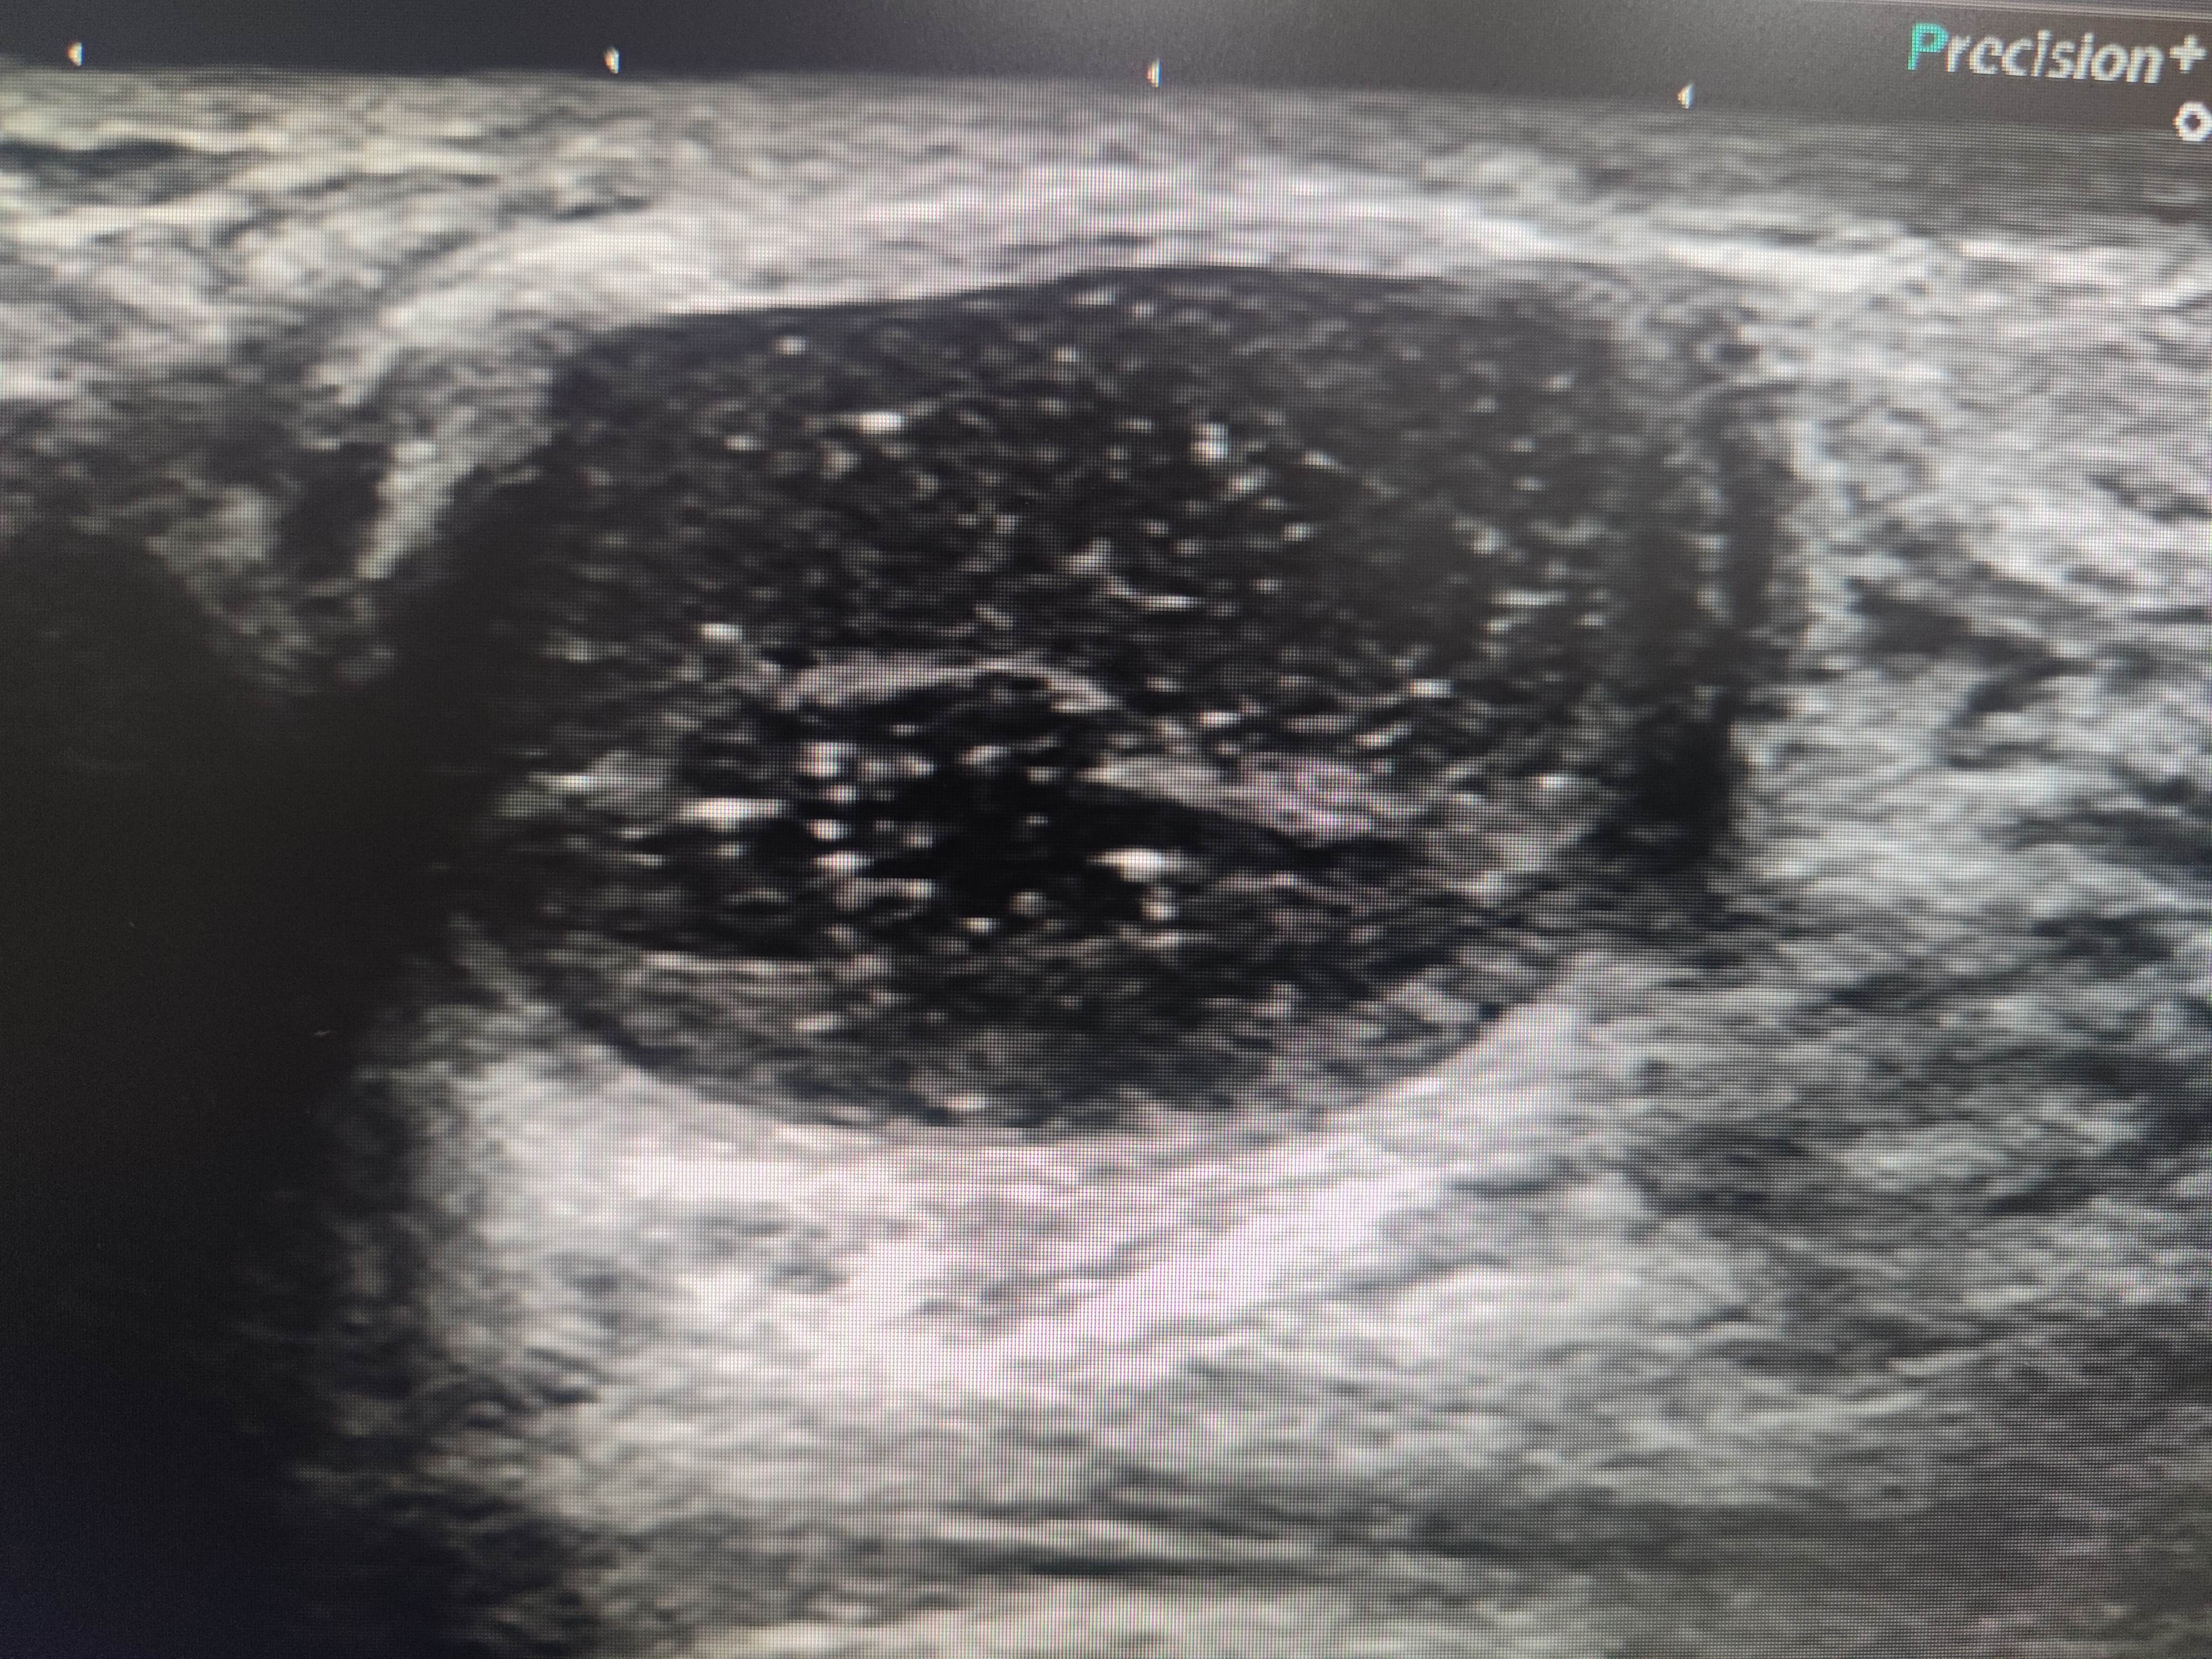

右侧乳腺12点乳晕后方腺体内可见一低回声包块,大小37✖️16mm,边界清,壁厚,内回声不均,可见数个彗星尾。来看看图,你们觉得该分几类?考虑是什么?